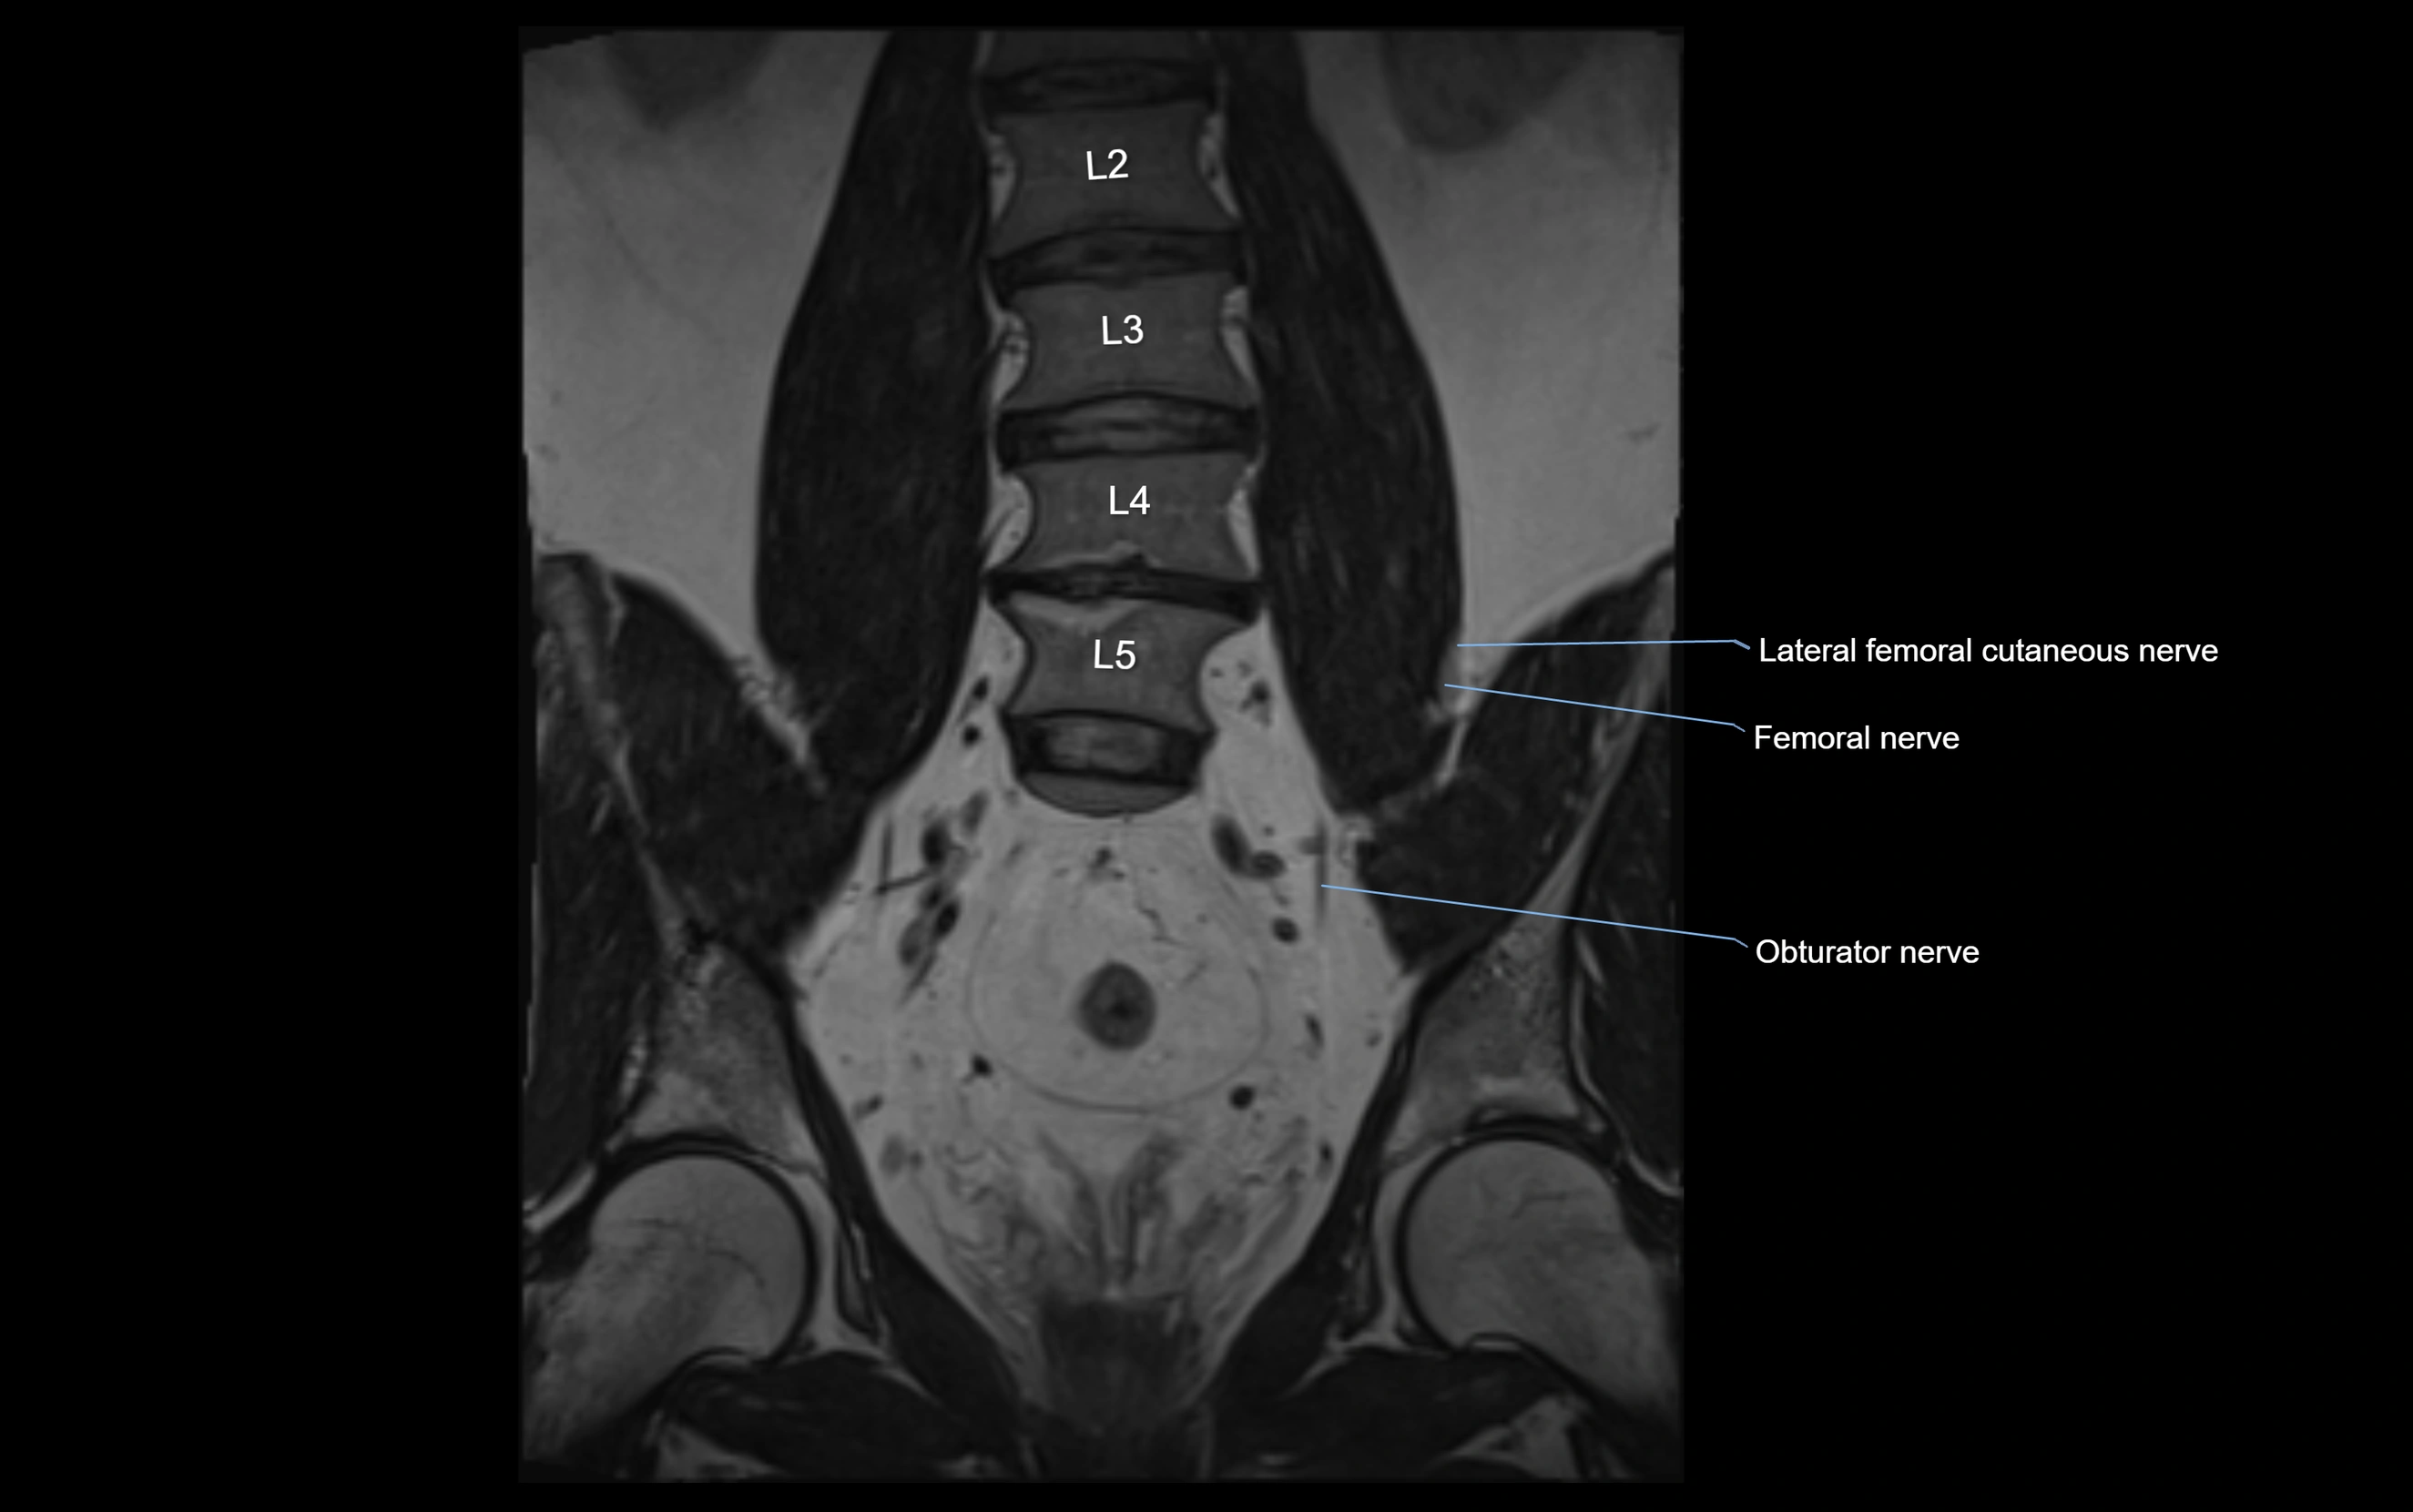

MRI image

image